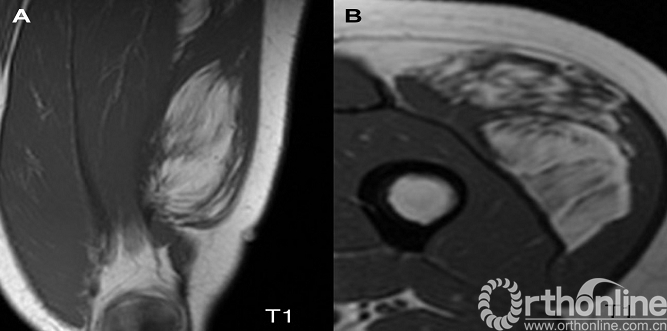

鉴别诊断:1.高分化脂肪肉瘤:在临床上,通常比脂肪瘤增长更快且更可能存在于深部组织。两者主要差异为高分化脂肪肉瘤在MRI上有更明显的分隔,表现为在T1低信号(暗)和T2高信号(亮)上可见不规则细线(图2)。2.肌内脂肪瘤(浸润性脂肪瘤):穿越肌层,产生异质的外观(图3),在某些情况下可能与高分化脂肪肉瘤混淆。3. 脂肪过多症:皮下脂肪增殖性疾病,非真正的肿瘤。常染色体显性遗传,典型表现为多发、柔软、无痛性肿块,分布在整个躯干和近端四肢(图4)。

图2.高分化脂肪肉瘤,T1加权像(A)和抑脂T2加权像(B)MRI序列,显示在内收肌间隙深部的脂肪肿块,两个序列均可见到肿瘤有明显的隔膜。

图3.浸润性脂肪瘤,冠状位(A)和轴位(B)T1加权像显示脂肪肿块,中间穿插有平行于股四头肌的粗大肌纤维;这种散在的肌纤维有时会误诊为脂肪肉瘤。